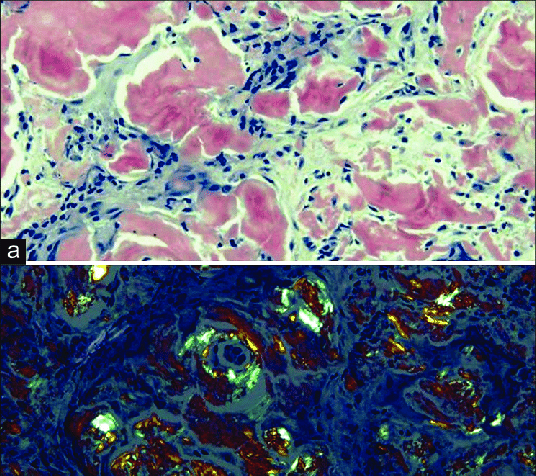

Which of the following describes the hyaline accumulation in the glomerulus that leads to sclerosis and is commonly associated with diabetes mellitus?

a) Amyloidosis

b) Fibrinoid necrosis

c) Hyaline arteriolosclerosis

d) Kimmelstiel-Wilson nodules

aka Diabetic glomerulosclerosis

Diabetic glomerulosclerosis, also known as Kimmelstiel-Wilson disease, is a kidney disease caused by diabetes that leads to the thickening and scarring of the glomeruli(the kidney's filtering units). This scarring, or sclerosis, is characterized by hyaline deposits and the formation of nodules within the glomeruli. It's a progressive complication of diabetes, potentially leading to chronic kidney disease and end-stage renal failure.

Which condition is characterized by extracellular hyaline-like material that shows apple-green birefringence on Congo red staining?

a) Fibrinoid necrosis

b) Lipofuscin accumulation

c) Kimmelstiel-Wilson nodules

d) Amyloidosis